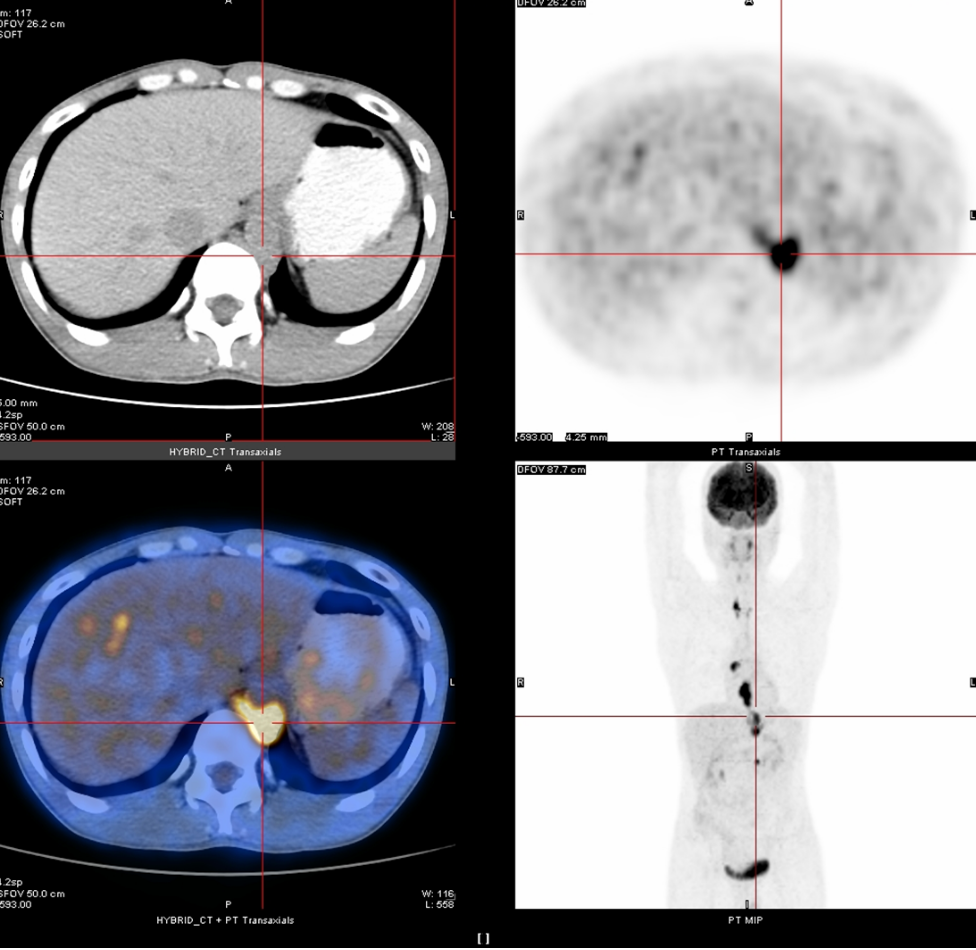

免疫治疗药物在食管癌二线甚至一线治疗中已经取得了令人振奋的临床疗效,人们也期待着其在新辅助治疗方面能够同样带来惊喜!本期我们将分享一例IVA期食管癌通过术前新辅助...

免疫治疗药物在食管癌二线甚至一线治疗中已经取得了令人振奋的临床疗效,人们也期待着其在新辅助治疗方面能够同样带来惊喜!本期我们将分享一例IVA期食管癌通过术前新辅助...